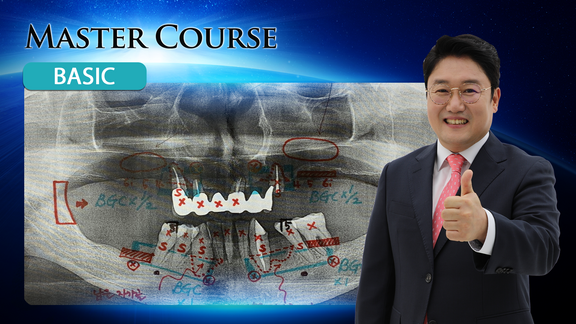

[BASIC] Radiology for Dental Implants

마스터코스

2020-02-20T00:00